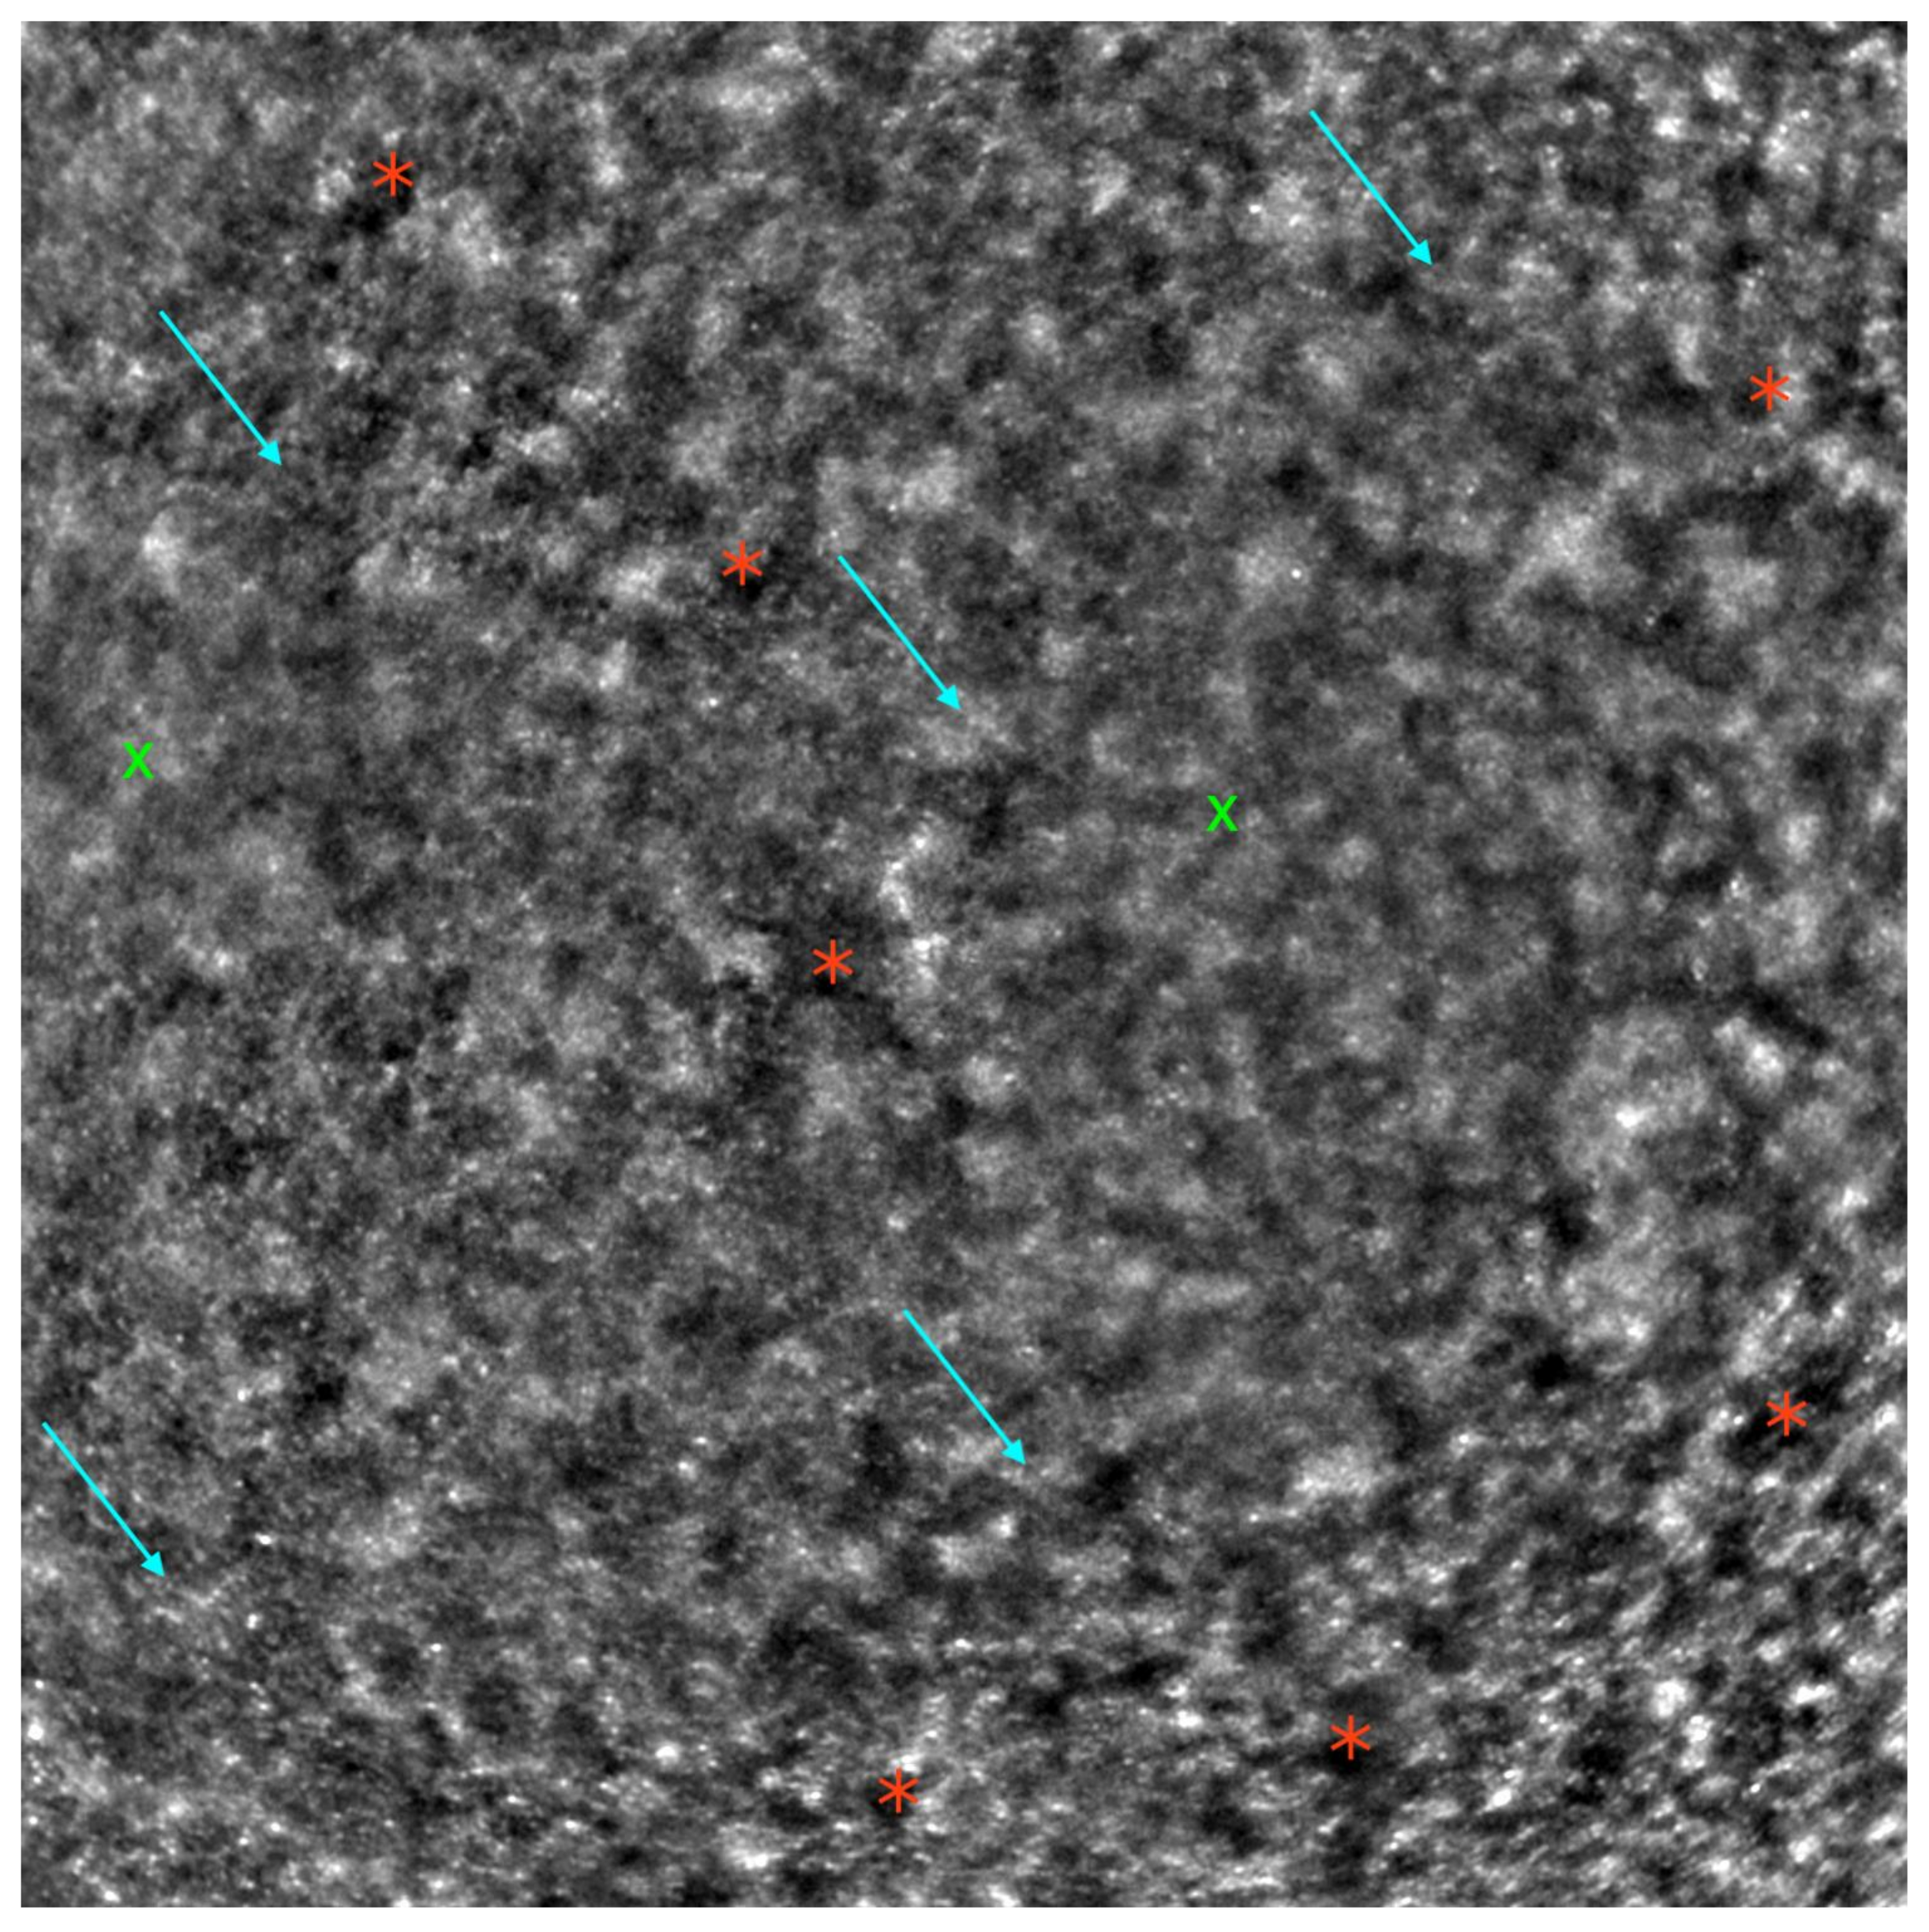

- Samelska, K.; Kupis, M.; Zaleska-Żmijewska, A.; Szaflik, J.P. Adaptive optics imaging in the most common inherited retinal degenerations. Klin. Ocz. 2021, 123, 74–79. [Google Scholar] [CrossRef]

- Gill, J.S.; Moosajee, M.; Dubis, A.M. Cellular imaging of inherited retinal diseases using adaptive optics. Eye 2019, 33, 1683–1698. [Google Scholar] [CrossRef]

- Zaleska-Żmijewska, A.; Wawrzyniak, Z.M.; Ulińska, M.; Szaflik, J.; Dąbrowska, A.; Szaflik, J.P. Human photoreceptor cone density measured with adaptive optics technology (rtx1 device) in healthy eyes: Standardization of measurements. Medicine 2017, 96, e7300. [Google Scholar] [CrossRef]

- Zaleska-Żmijewska, A.; Wawrzyniak, Z.M.; Dąbrowska, A.; Szaflik, J.P. Adaptive Optics (rtx1) High-Resolution Imaging of Photoreceptors and Retinal Arteries in Patients with Diabetic Retinopathy. J. Diabetes Res. 2019, 2019, 9548324. [Google Scholar] [CrossRef]